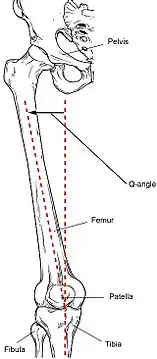

Additionally, female pelvises widen during puberty through the influence of sex hormones. This wider pelvis requires the femur to angle toward the knees. This angle towards the knee is referred to as the Q angle. The average Q angle for men is 14 degrees and the average for women is 17 degrees. Steps can be taken to reduce this Q angle, such as using orthotics.[22] The relatively wider female hip and widened Q angle may lead to an increased likelihood of ACL tears in women.[23]